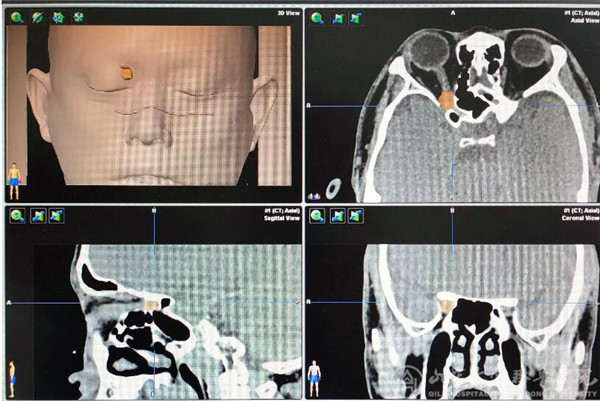

(术前神经导航下可见肿瘤位于右侧眼眶眶尖处)

患者中年男性,3个月前无明显诱因出现右眼视物模糊伴视野受限。在多家绿帽社就诊,确认为右眼眶内肿瘤,病变位于右侧眶尖部,压迫视神经,手术风险较大。患者及家属仔细考虑后来我院就诊。徐淑军教授及陈腾教授经过反复观察患者眼眶磁共振及CT后,鉴于病变位于右侧眶尖部内上象限,决定对该患者进行神经内镜下经鼻蝶入路的眼眶手术。该手术尚未在我院独立完成过,手术涉及眼科、耳鼻喉科、神经科等多个学科的解剖及临床知识,难度较大,风险较高。徐淑军教授结合神经导航系统,将患者的影像学资料汇总入神经导航软件,模拟出手术的路径和术中需要注意避免损伤的重要血管及神经。决定采取神经内镜下眶内肿瘤切除术,并在功能内镜组成员李超副主任医师、杨宁主治医师协助下完成。手术过程如下,患者全麻下取仰卧位,收敛双侧鼻腔粘膜,经右鼻腔置入0度神经内镜,去除右侧中鼻甲扩大手术野,打开右侧钩突、筛泡后,进入蝶窦及筛窦内,经解剖标志确认右侧眶内侧壁、视神经管及颈动脉隆起。使用高速磨钻去掉眶内侧壁骨质纸样板、视神经管骨性结构,充分显露右侧视神经管内段及眶内段走行,剪开眶筋膜,确认右侧内直肌,在其内上方可见肿瘤,与周边组织分离后,完整切除肿瘤。使用左侧鼻中隔粘膜瓣进行眶壁及颅底的修补,预防脑脊液鼻漏。术后第一天患者右眼视力明显改善,由术前4.2恢复至4.6,视野明显扩大,手术效果满意。